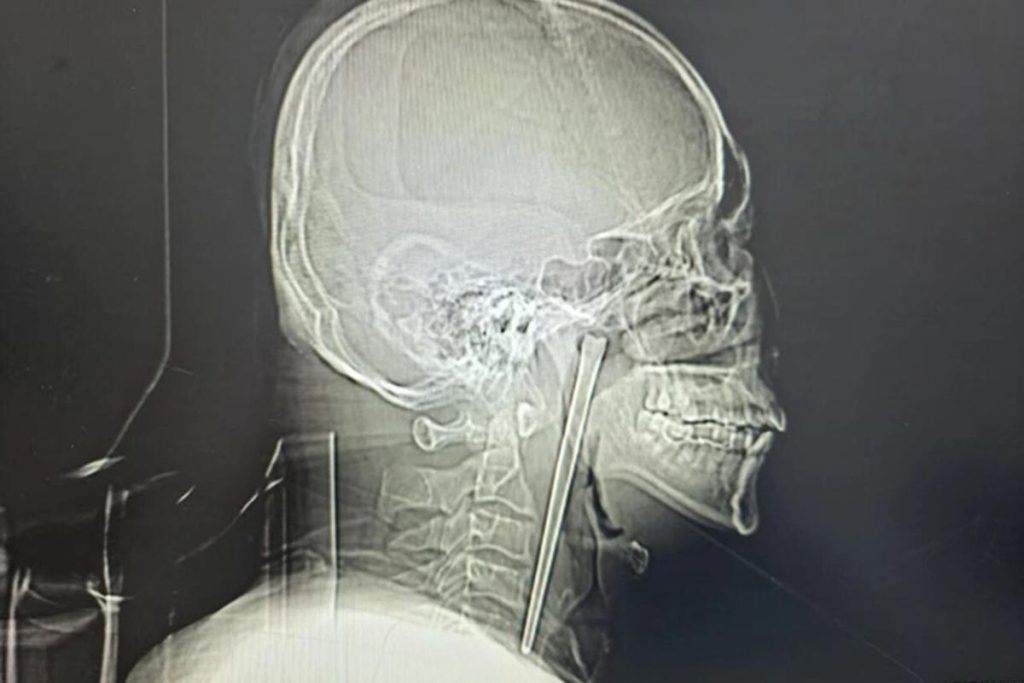

A man in China swallowed a metal chopstick while eating dinner eight years ago and decided to leave it lodged in his throat until a surgeon finally removed it last month, March 2026.

According to a jaw-dropping hospital case study published in March, the “alcoholic” patient, identified only as Mr. Wang, went in for a check-up shortly after gulping down the five-inch utensil in 2018 but refused to have it removed.

Wang, 46, didn’t want doctors to cut his neck open at the time, so he lived with the discomfort for years, the South China Morning Post reported.

It became increasingly harder for him to swallow several weeks ago, so he asked doctors at Dalian Municipal Central Hospital in Liaoning Province to take a look.

Surgeons performed a minimally invasive operation to remove the obstructive object via Wang’s mouth instead of slicing open his neck, according to the hospital’s report.

His vocal cords and nearby mucous membrane were luckily not injured and functioned normally after the surgery, according to the report.

Wang was discharged from the hospital days later and is expected to make a full recovery.